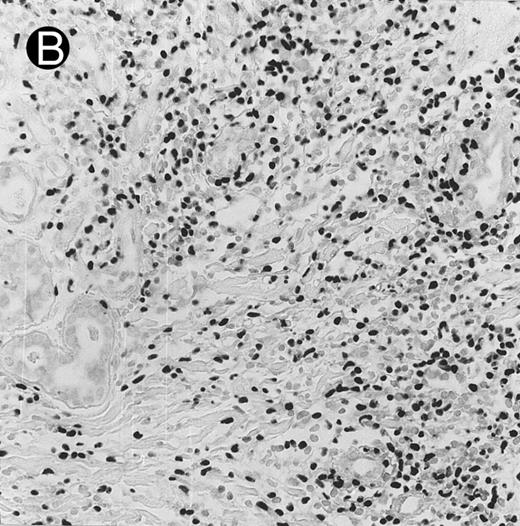

Lymph node biopsy of aggressive NK cell leukemia/lymphoma (case no. 37). There is a fairly monotonous, diffuse infiltrate of medium-sized cells with round nuclei. The neoplastic cells in this case resemble plasmacytoid monocytes.

There were very few to numerous granular lymphocytes in the peripheral blood. Some of the granular lymphocytes were indistinguishable from normal large granular lymphocytes, with round nuclei, dense chromatin, and pale cytoplasm with fine azurophilic granules (Fig 5A). Some granular lymphocytes had larger nuclei with more open chromatin and distinct nucleoli (Fig 5B); occasional nuclei could show indentations. The azurophilic granules were sometimes large and coarse. There were also circulating normoblasts and immature myeloid cells. Marrow involvement ranged from subtle to extensive. In histologic sections, irrespective of site, there was a monotonous infiltrate of medium-sized cells with round nuclei and fairly condensed chromatin (Fig 6). Karyorrhexis was prominent. The infiltrate was diffuse, interstitial, or angiocentric.